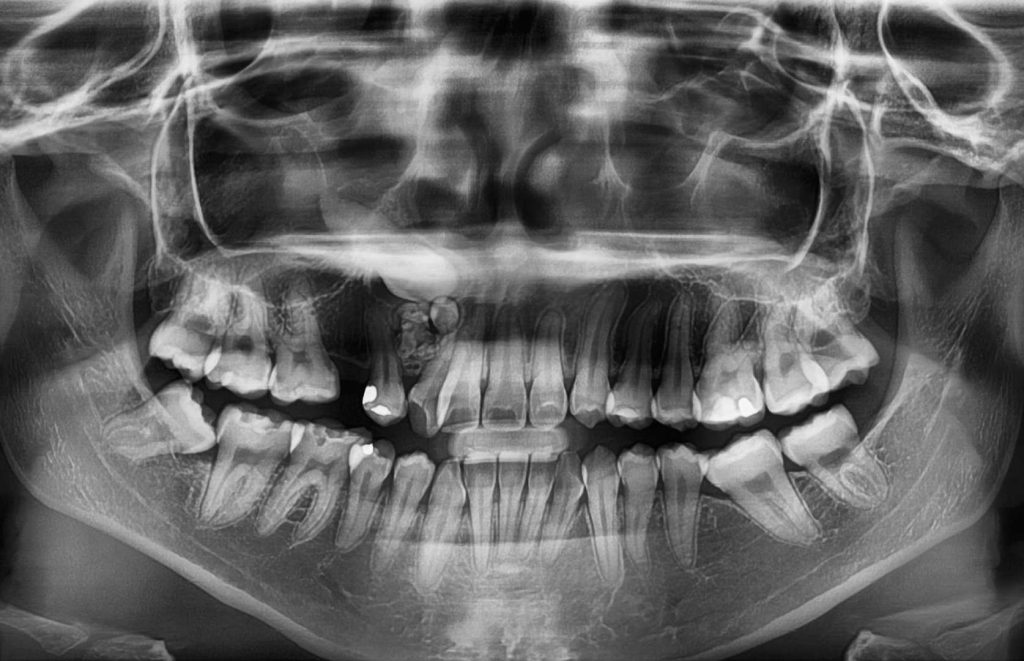

ادونتومها

ادونتومها تومورهای خوشخیم دندانی هستند که میتوانند به شکل یک دندان اضافی یا مجموعهای از دندانهای کوچک ظاهر شوند. این شایعترین نوع تومور دندانی است که در نوجوانی یا اوایل بزرگسالی تشخیص داده میشود. علائم اغلب وجود ندارد اما میتواند شامل درد، تورم و تاخیر در رشد دندانهای دائمی باشد.